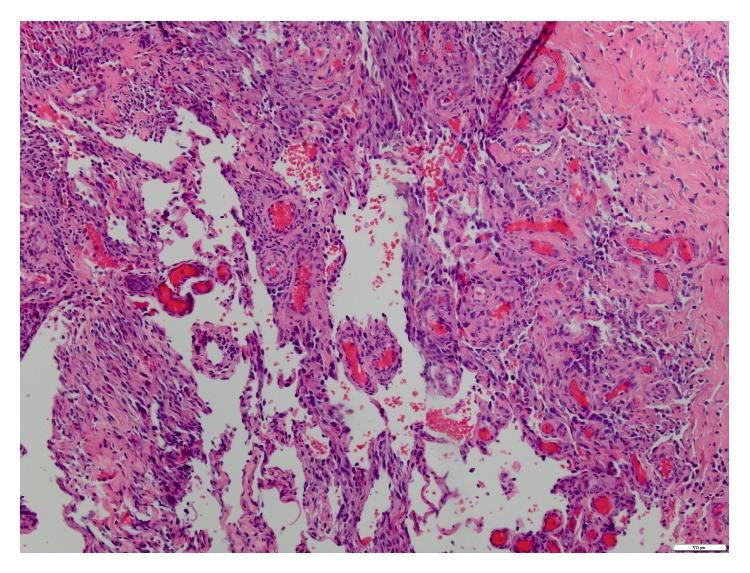

Primary Angiosarcoma of the skin of the foot is very rare. Angiosarcoma is typically treated with resection and wide-field postoperative radiation therapy. Chemotherapy and radiation therapy have also been used. Regardless of the treatment, the risk of local and distant relapse remains high for this disease. We present a case of an elderly patient who developed cutaneous angiosarcoma of the foot. It posed as a diagnostic dilemma at presentation. Chronic lymphedema was a possible predisposing factor. Given his age, preexisting renal dysfunction, refusal of surgery, and preference not to receive chemotherapy, the patient was ultimately treated with definitive radiotherapy. We present this case because of its rare site, unique presentation and delay in diagnosis of the condition, and attainment of an excellent response to radiation at the time of follow-up. We also review the current literature on this topic.

足部皮肤原发性血管肉瘤非常罕见。血管肉瘤通常采用手术切除及术后大范围放射治疗。也有人使用化疗和放射治疗。无论采用何种治疗方法,这种疾病的局部和远处复发风险仍然很高。我们报告一例老年患者足部发生皮肤血管肉瘤的病例。该病例在初诊时构成诊断难题。慢性淋巴水肿可能是一个诱发因素。鉴于患者年龄、已存在的肾功能不全、拒绝手术以及不愿接受化疗,该患者最终接受了根治性放疗。我们报告此病例是因为其发病部位罕见、表现独特、诊断延迟,以及随访时放疗取得了极佳疗效。我们还回顾了关于该主题的当前文献。